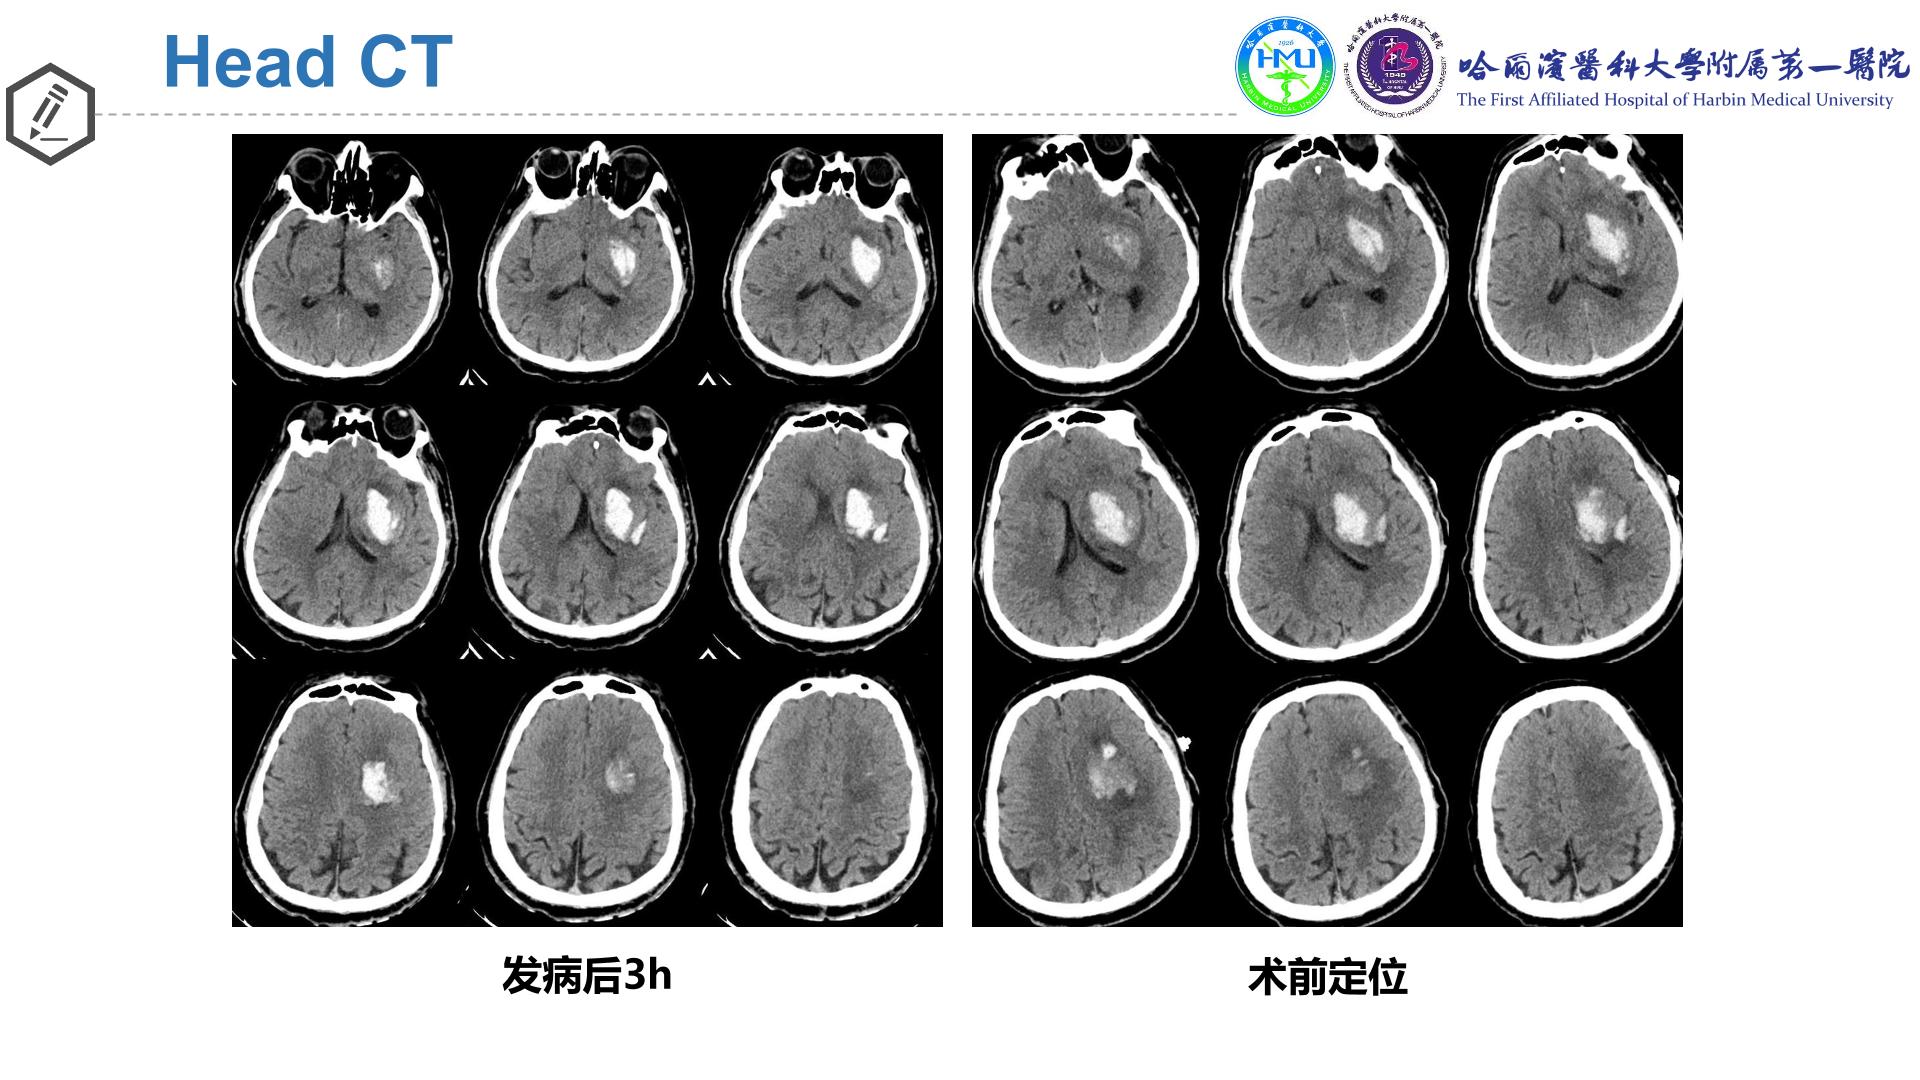

神经导航辅助内镜下清除左侧基底节区脑出血

术后14d

完全性混合性失语→不完全性运动性失语

右下肢肌力0→III级